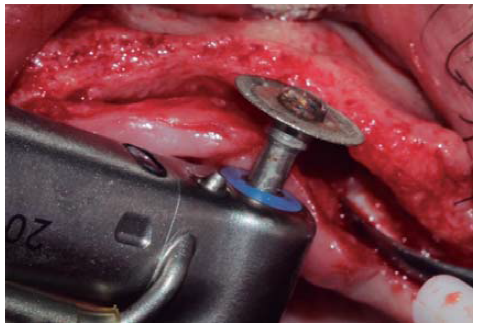

A full thickness incision over the crest was performed, raising a mucoperiosteal flap exposing bone table up to 4 mm from the top of the crest in vestibular direction; from that point the flap was divided into partial thickness (Figure 3). After this, impact points were marked in designated places according to surgical guide for implant placement; perforations were initiated with a 1.6 mm diameter burr in order to determine desired implant depth and axis. After this, a ridge was created on the crest with a diamond burr, fracturing cortical bone to create chisel's access to cancellous bone, and with the aforementioned, bone tables were separated until reaching a 5 mm depth (Figures 4 y 5). Perforations were further continued with a 2.0 diameter burr (Figure 6), and vestibular table expansion was undertaken creating greenstick fracture with the expanders, until reaching sufficient osseous bed diameter (3.2 mm diameter) (Figures 7 y 8). Implants were then placed at a 25 rpm speed and 35 Nem torque (Figures 9 y 10). After this, a particulate bovine bone graft was placed (Bonefill® Bionnovation Biomedical, Sao Paulo, Brazil) with the aim of preserving integrity of vestibular bone tables (Figure 11). All these procedures were repeated for placement of all six implants. Finally, sutures were undertaken with monofilament nylon 5/0.

Figure 4 Diamond disc (0.5 mm thick) used to create a crest groove passing through cortical bone and allowing access for bone chisel.